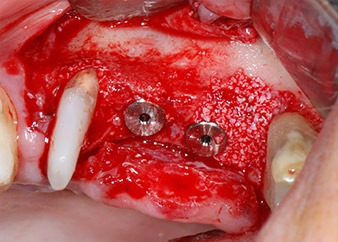

The implants (Restore, Keystone Dental, diameter 3,75 mm, length 8.0 mm) were placed with the implant motor

(Figs. 11 and 12).

ready for the cover screws

Fig. 12: Both implants in place and ready for the cover screws.